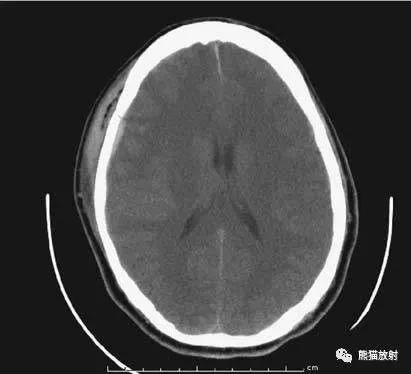

6、脑梗死

缺血性脑卒中早期:脑水肿,灰白质分界模糊,脑沟消失;

中期:病变区域密度减低;

晚期:脑实质体积缩小。

A:陈旧性脑梗死,右枕叶体积缩小;

B:左枕叶急性脑梗死,灰白质分界模糊,脑沟消失;

另一患者:

C、D:亚急性期脑梗死,低密度,无明显占位效应。

▲左侧大脑中动脉供血区脑梗死(亚急性期):

低密度,轻度水肿。

缺血性脑卒中发作2-4天时,占位效应最明显。